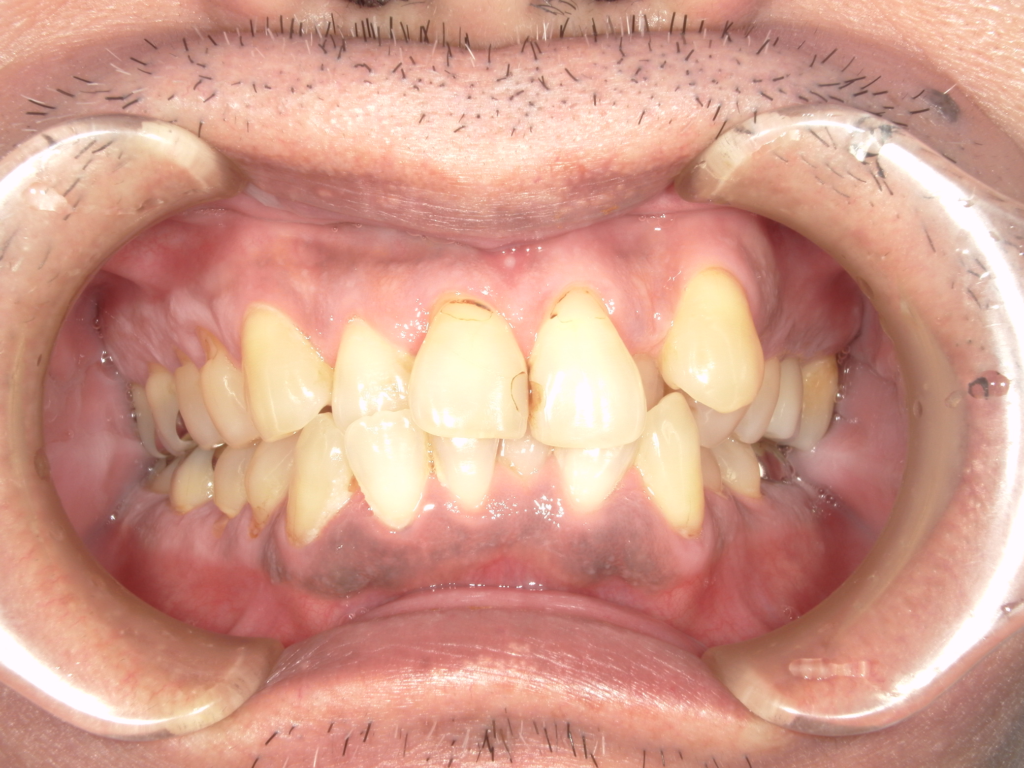

Y様インプラント実例 #44

左の上下の奥歯をインプラントで治療しています。

左下の奥歯は歯を抜くのと同時にインプラントの埋め込みを行っています。

被せものは上下、セラミックスで作っています。

治療前

治療後